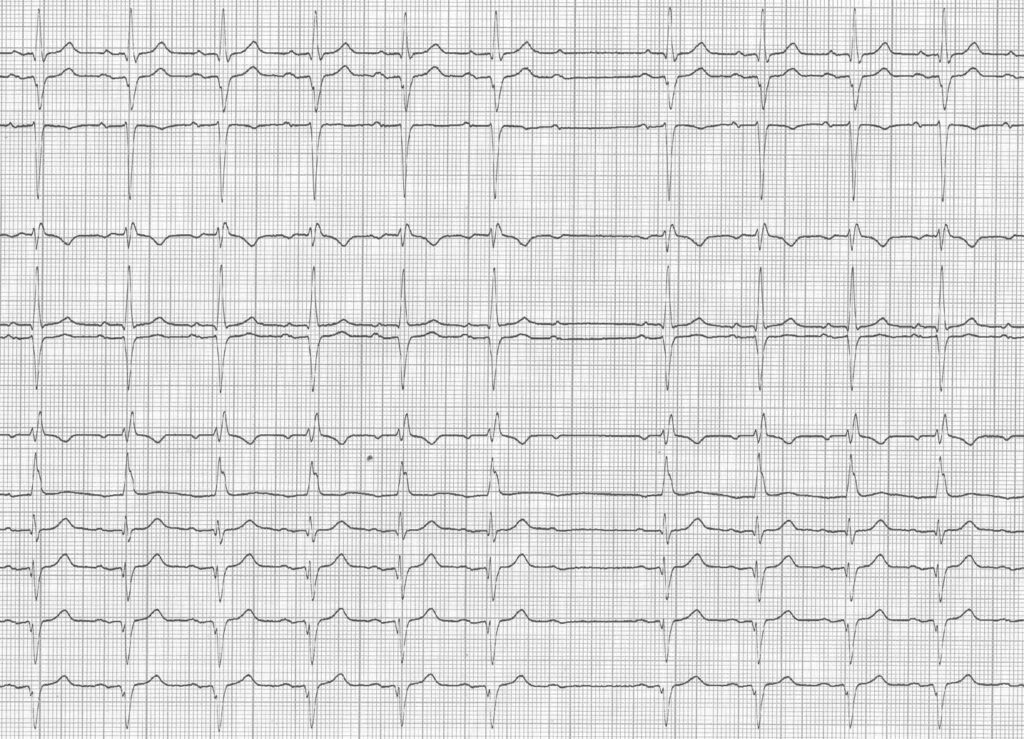

• Comme chez ce patient, les complexes ventriculaires sont le plus souvent anormaux; plus rarement une morphologie normale (QRS fin) est observée.

Ce type de BAV II type 2 est la plupart du temps la conséquence d’une lésion anatomique dégénérative irréversible. L’enregistrement des potentiels du faisceau de His montre que l’origine du blocage intermittent se situe habituellement dans la partie distale du faisceau de His ou dans une des trois branches, les 2 autres étant déjà bloquées (bloc intra- ou infra-hisien). Cela explique la constance de l’espace PR avant et après l’onde P bloquée, la conduction se faisant selon le principe du tout ou rien.

Ce type de tracé est une indication indiscutable de pose de stimulateur. En effet, la progression vers le BAV III est fréquente; de plus, en raison de la localisation du bloc, les échappements potentiels sont bas situés et sont souvent lents et instables majorant le risque de syncope ou de mort subite.